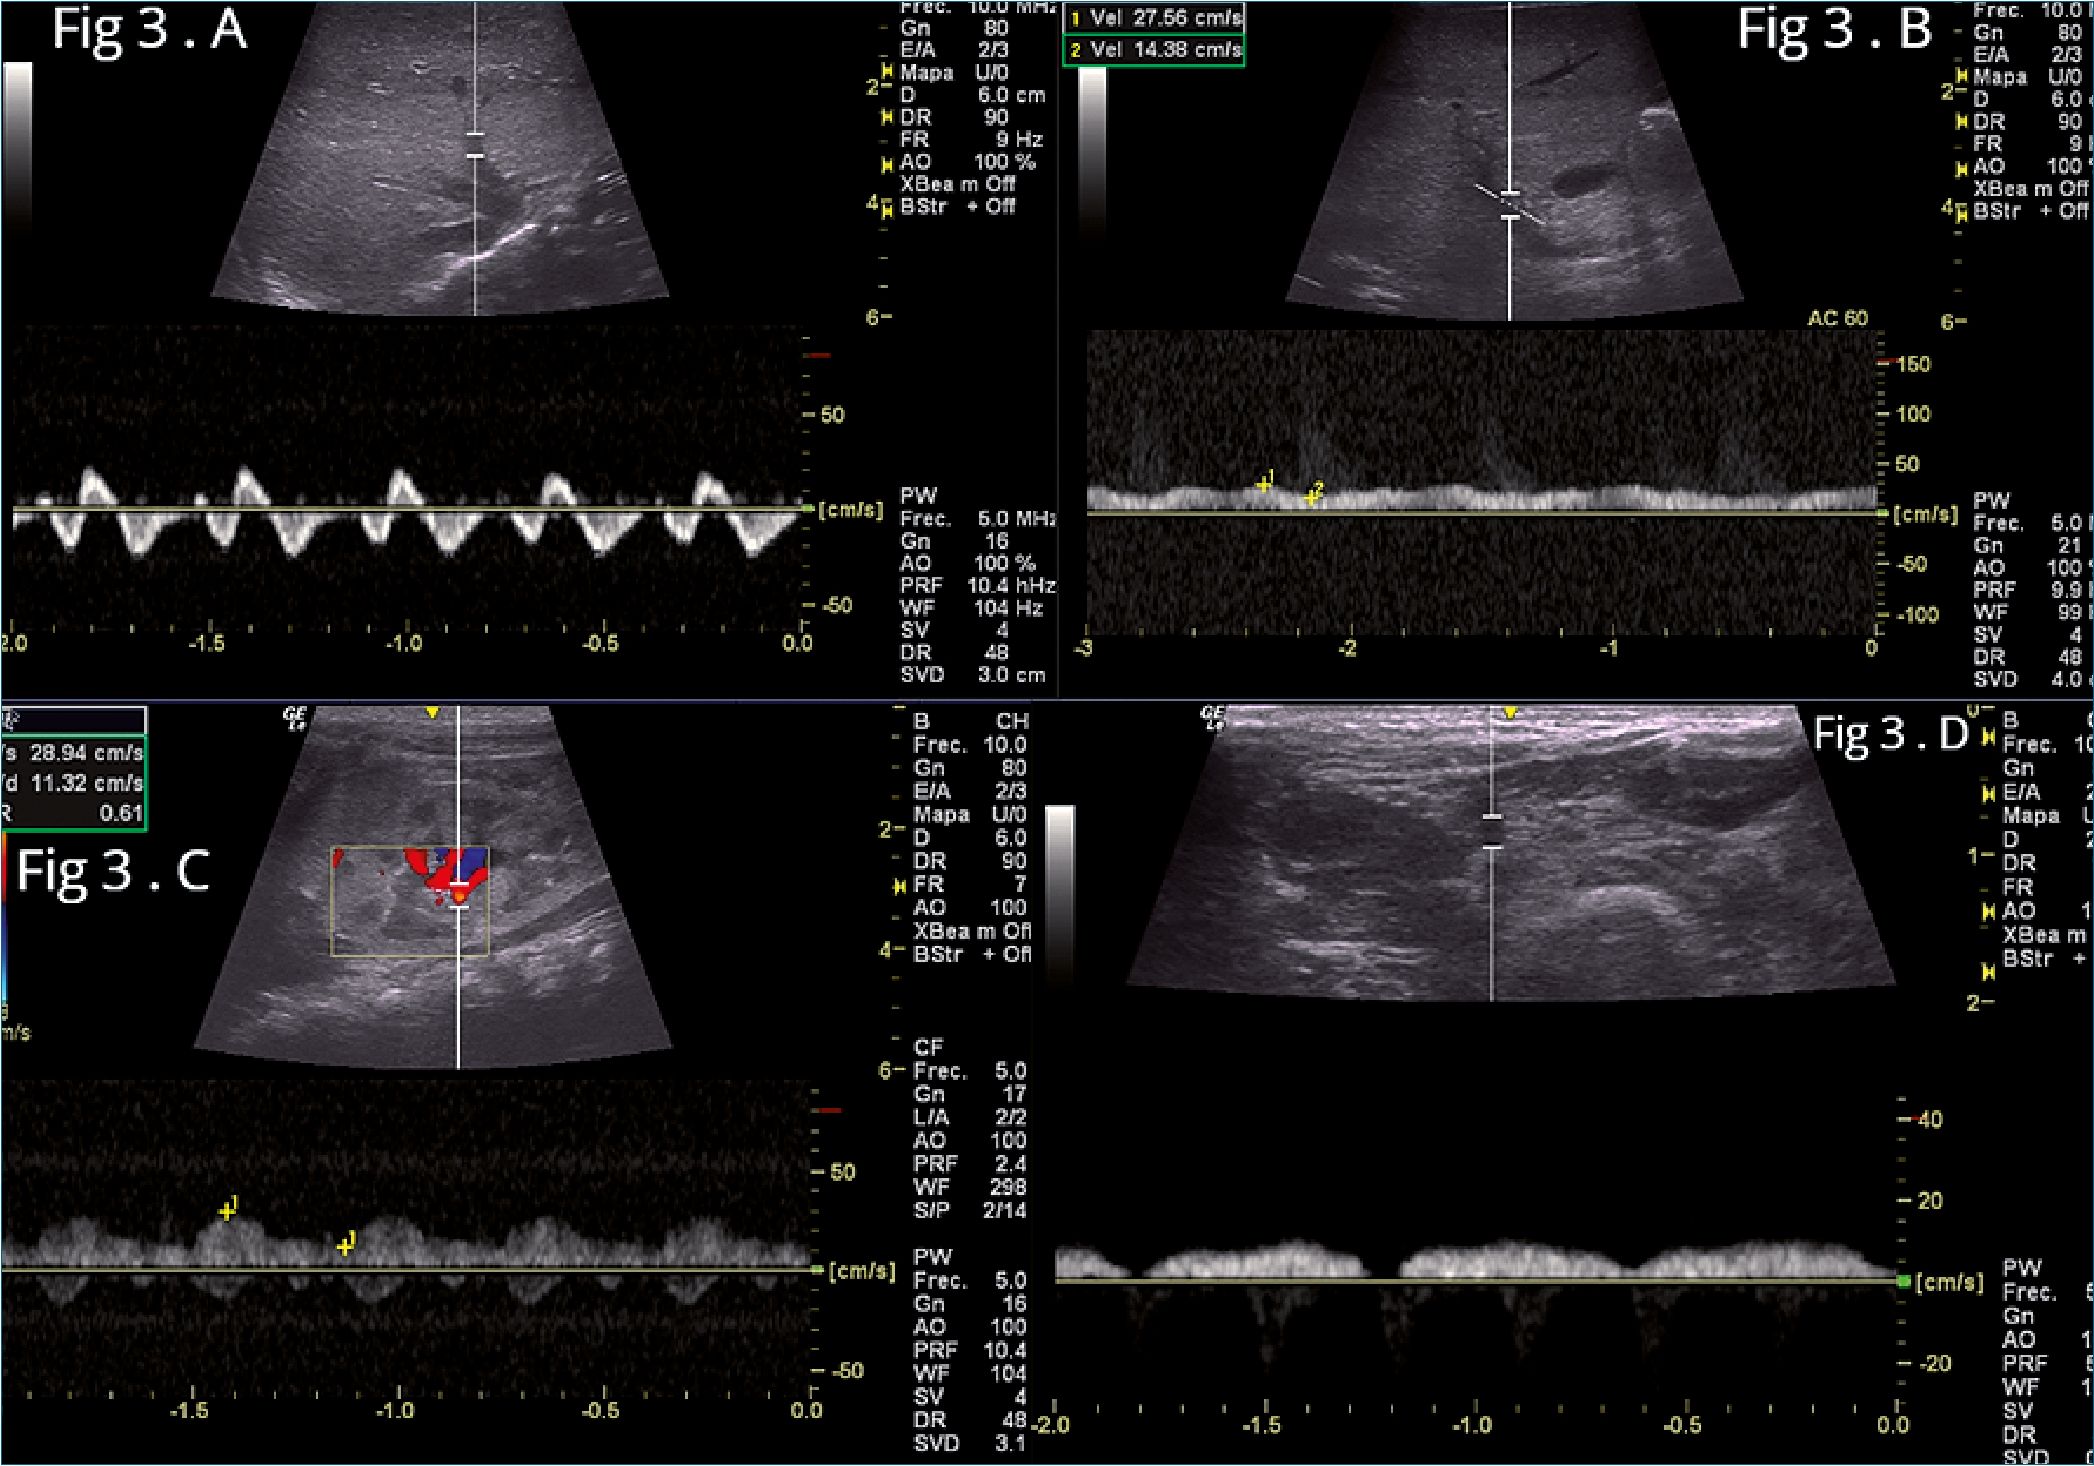

Al 7° día: el ecocardiograma muestra: dilatación de cavidades derechas con disfunción VD: TAPSE 7 mm, hipertensión pulmonar leve, PASP: 40 mmHg. El VI no está dilatado y con función sistólica normal. FAVI: 31%, se suspende soporte ino- trópico. Derrame pericárdico leve de 5 mm. Persiste, aunque en menor grado, la alteración del flujo de las venas abdominales y femorales secundaria a la disfunción del VD (Figura 3 A-B-C-D).

Figura 3. Flujos venosos después de 7 días de tratamiento. A: Flujo de la vena suprahepática, Trifásica con onda S > D y onda A persiste acentuada; B: Flujo de la vena porta, Pulsatilidad inferior: IP < 30%; C: Venas y arteria renal, vena renal pulsátil bifásica IRR: 0,61; D: Flujo de la vena femoral común, vena femoral con pulsatilidad disminuida.

En la evolución notamos la mejoría de los patrones espectrales inicialmente en los territorios venosos más distales, pero la normalización de todos los flujos solo fue evidente a las 2 semanas.